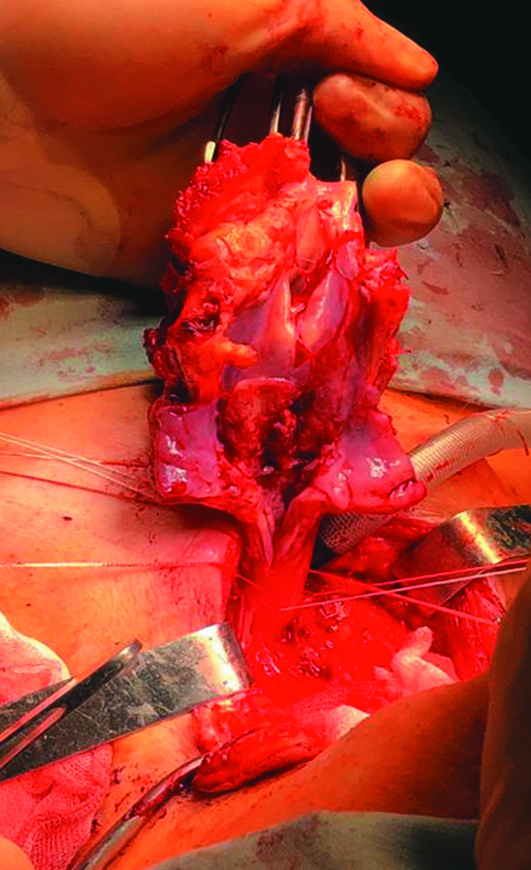

The surgical stages are presented in Figures 2–6.

Figure 4. Radial flap dissection, radial artery and vein are tagged

Рисунок 4. Выделение лучевого лоскута, выделены лучевая артерия и вена.

Figure 5. The flap size 15 x 6 cm. Adaptation of the microsurgical flap – formation of a tubular structure with a diameter of up to 2,5 cm, and 15 cm of length

Рисунок 5. Выделенный лоскут размерами 15х6 см. Выполнена адаптация микрохирургического лоскута – сформирована трубчатая структура диаметром до 2,5 см, длиной 15 см.

Figure 6. Formation of the pharyngeal-esophageal tube from the radial flap of the forearm, matching the edges of the flap with the esophagus and pharynx. Microvascular anastomosis of the vessels of the radial flap with the recipient vessels was performed: the left facial artery and vein, the anastomoses are consistent, the blood flow is restored

Рисунок 6. Формирование глоточно-пищеводной трубки из лучевого лоскута предплечья, сопоставление краев лоскута с пищеводом и глоткой. Выполнено микрососудистое анастомозирование сосудов лучевого лоскута с реципиентными сосудами: левые лицевая артерия и вена, анастомозы состоятельны, кровоток восстановлен.